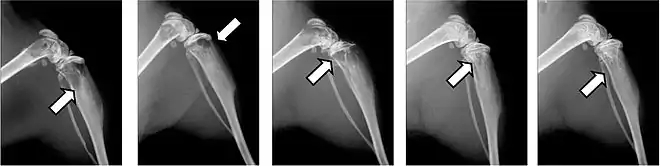

Fractures pathologiques

La fracture pathologique est une circonstance rare de découverte d'une métastase osseuse[75],[76].

Les fractures pathologiques sont des fractures de l’os qui surviennent sans atteinte extérieure, à cause d'un affaiblissement pathologique de la matrice osseuse. Les métastases surtout ostéolytiques, mais aussi parfois ostéocondensantes, affaiblissent l’os concerné qui selon les circonstances peut être sursollicité par des contraintes mécaniques faibles, et rompt. Ces fractures peuvent survenir dans des situations de tous les jours, comme le fait de se lever d'un siège ou de déplacer le patient[77]. Pour les métastases ostéocondensantes, l'épaisseur de l’os est certes augmentée, mais sa solidité est abaissée par sa construction complètement non structurée[6]. Dans le domaine de la colonne vertébrale, elles peuvent conduire à des enraidissements[65].

Les fractures pathologiques conduisent à des complications étendues et ont une influence considérable sur la qualité de vie et sur le pronostic. La durée de survie moyenne peut être diminuée de plusieurs mois[22]. Les bisphosphonates peuvent éviter dans bien des cas cette forme de fracture[78],[79].

Ce sont la plupart du temps les côtes ou les corps vertébraux qui sont atteints par les fractures. Les fractures dans les os longs, en particulier au col du fémur, présentent une gravité particulièrement élevée et sont le principal motif pour une intervention chirurgicale. Les fractures des corps vertébraux peuvent conduire à des syndromes de compression médullaire[65].

- Vues de fractures pathologiques

Fracture pathologique de l'humérus sur une métastase de carcinome du rein

Fracture pathologique de l'humérus sur une métastase de carcinome du rein Fracture pathologique du bras gauche sur une métastase osseuse de cancer du sein

Fracture pathologique du bras gauche sur une métastase osseuse de cancer du sein Scintigraphie corps entier avec 99mTc-HDP de la patiente avec une fracture du bras due à une métastase du cancer du sein

Scintigraphie corps entier avec 99mTc-HDP de la patiente avec une fracture du bras due à une métastase du cancer du sein